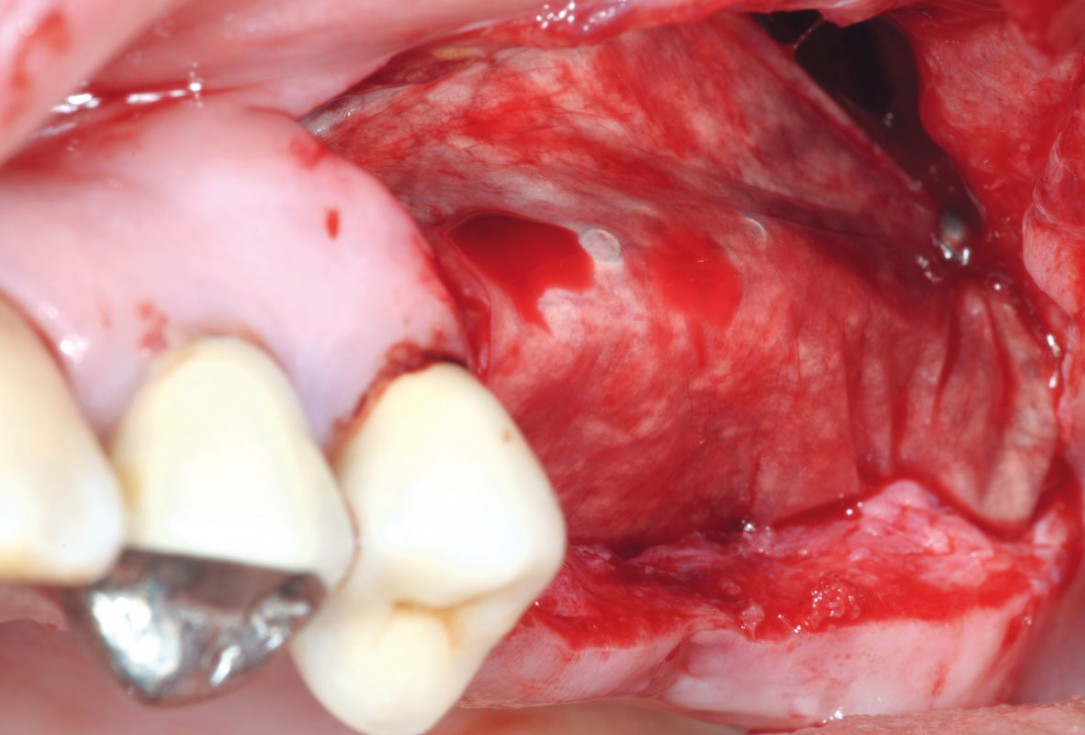

8/15 - Clinical situation five months after augmentation, time of re-entryTreatment of a combined horizontal and vertical bone defect in the maxilla with maxgraft® cortico in the allogenic shell technique - Dr. R. Würdinger